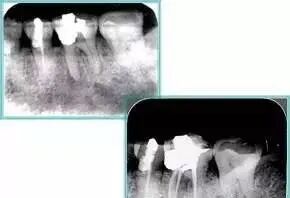

左图为根管充填术后 X 线片。图中可见,根管充填较好。右下图有白色小点,为侧方加压导致糊剂挤出所致,表明根管充填比较致密。